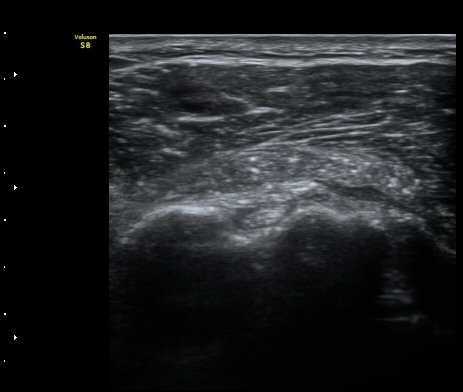

À̵ιڱ٠Ⱦ´Ü¸é°Ë»ç¿¡¼­ Á¡¾×³¶³» °í¿¡ÄÚ ¼®È¸È­ À½¿µµéÀÌ °üÂûµÊ(±×¸² 1, 2, 5)

À̵ιڱ٠Á¾´Ü¸é°Ë»ç¿¡¼­µµ Á¡¾×³¶³» ¼®È­È­ À½¿µÀÌ °üÂûµÊ(±×¸² 4).